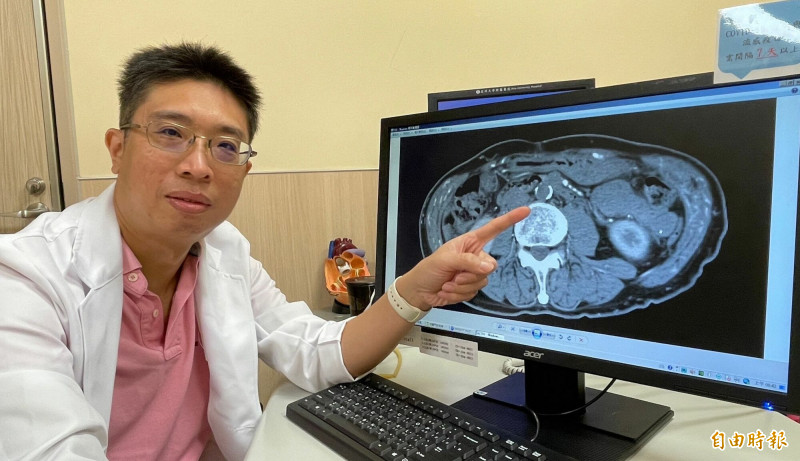

亞大醫院心臟外科主任劉殷佐表示,患者到院時幾乎是拖著腳跛行走進診間,不斷表示疼痛造成生活品質極差,「走幾步就得休息一下」,先透過觸診檢查雙側股動脈,發現脈搏十分微弱,足背及脛後動脈也察覺不出脈動,懷疑可能是血管阻塞,立刻安排電腦斷層檢查,果然找出從肚臍上8公分處以下主動脈及雙側總腸骨動脈完全阻塞,且雙側外腸骨動脈狹窄。

劉殷佐表示,影像檢查顯示,患者的腹主動脈、髂骨動脈以及上腸繫膜動脈等,都有阻塞情形,確認為「髂主動脈血管阻塞症候群」,此病主要特徵會以跛行、雙下肢脈搏下降、勃起困難表現,因此也俗稱「腳中風」。